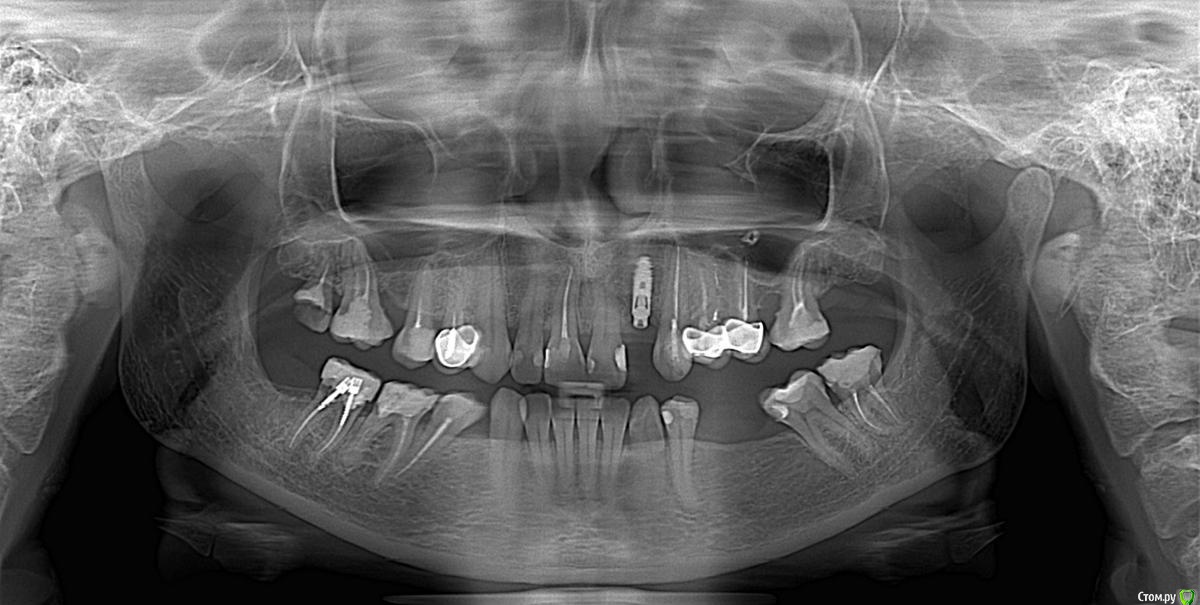

red_butler Опубликовано 17 апреля, 2015 Поделиться Опубликовано 17 апреля, 2015 покажите Rg снимок Ссылка на комментарий

nat-man Опубликовано 17 апреля, 2015 Автор Поделиться Опубликовано 17 апреля, 2015 снимок сделан в день перед установкой формирователя Ссылка на комментарий

red_butler Опубликовано 17 апреля, 2015 Поделиться Опубликовано 17 апреля, 2015 спасибо, а кто проводит такие операции? сам хирург-имплантолог который ставил имплант? почему сложилась такая ситуация с десной? это моя вина или из-за слишком высокого уровня установки импланта? спасибо.делает хирург который это умеет, да имплант поставлен слегка выше. Покажите фото своей улыбки Ссылка на комментарий